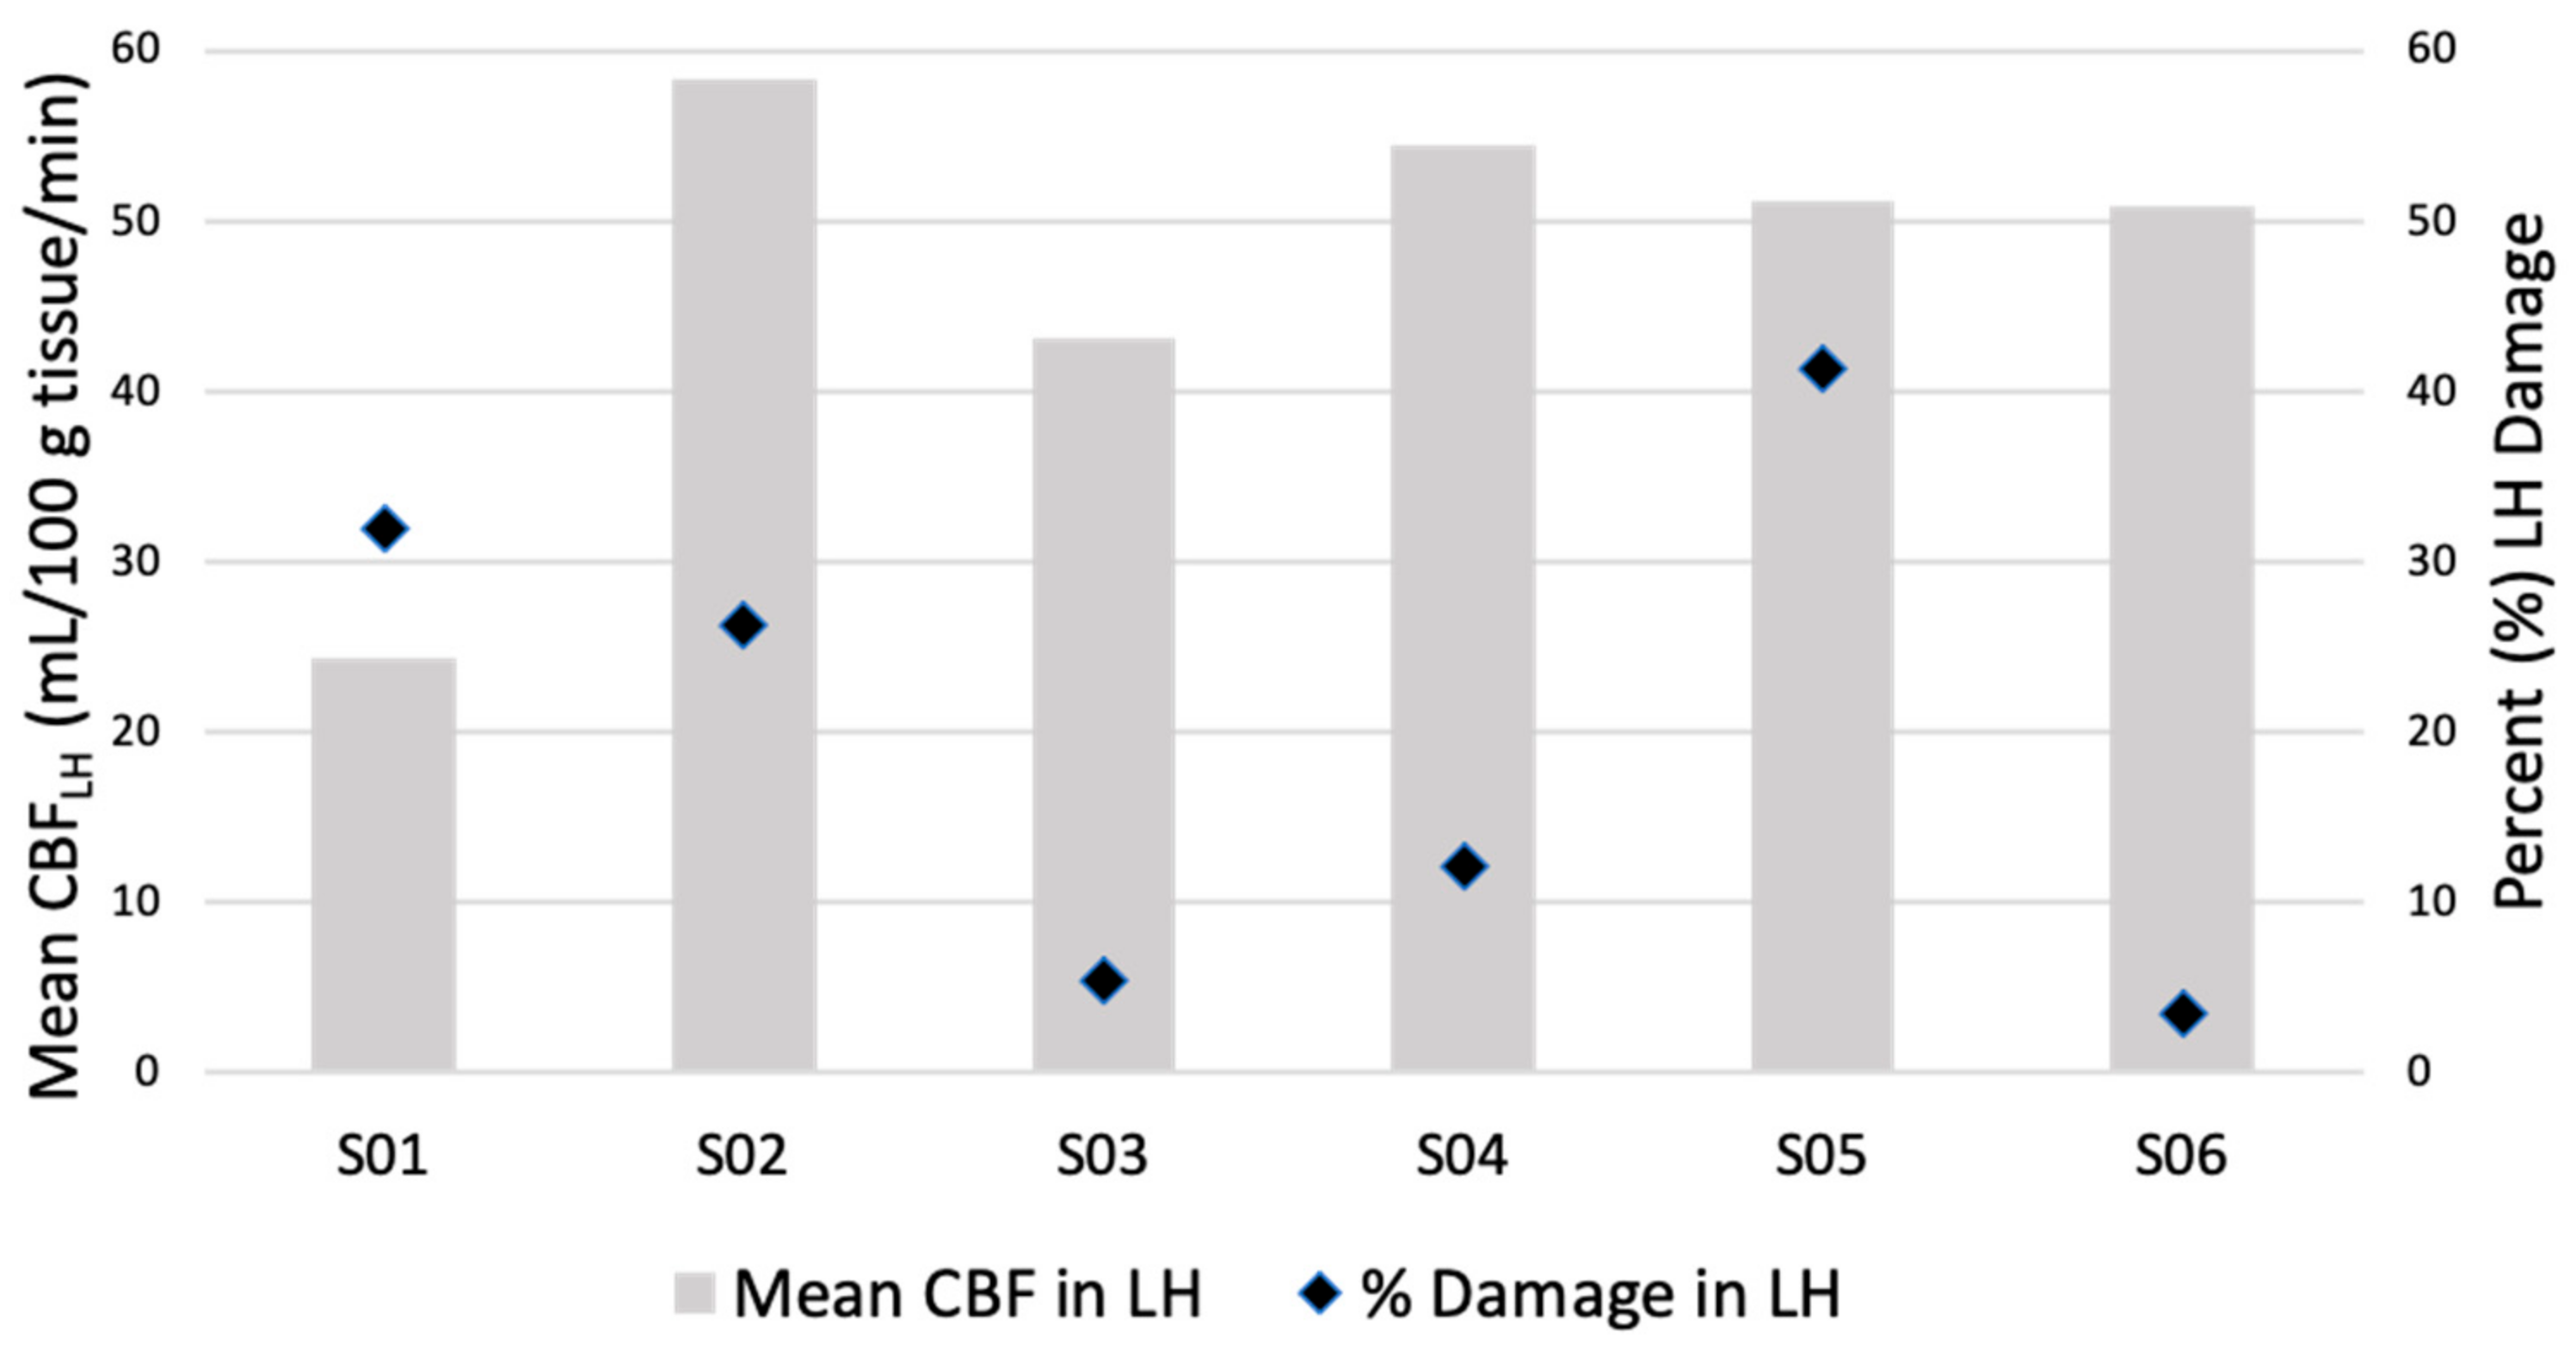

4.1. CBF Comparisons: Left Versus Right Hemisphere

4.2. Lesion Size and CBF

4.5. Identifying Hypoperfused Tissue in Language Regions

4.6. Hypoperfusion and Language Behavior